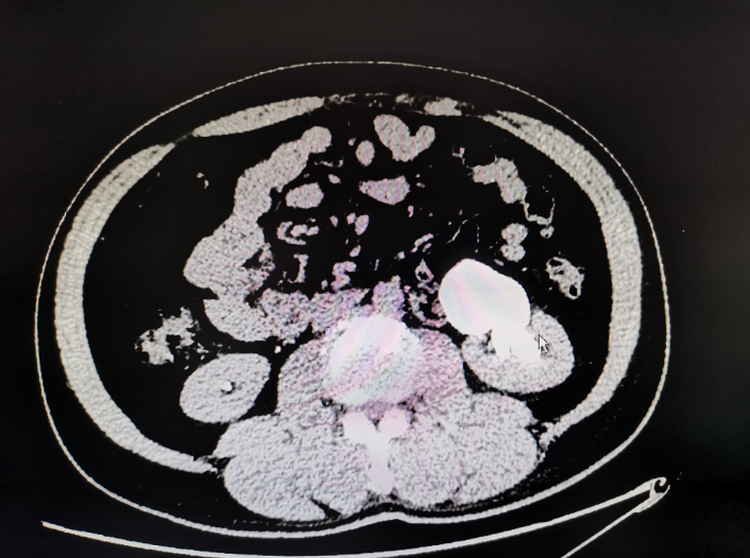

一例31岁男性患者,因“右侧腰背区疼痛1天”,行CT考虑为腔静脉后异位输尿管致肾积水,完善术前准备后为其行了"经腹腹腔镜下腔静脉后输尿管成形术",手术顺利,患者已出院。

一例为47岁男性患者,因“体检发现左肾积水”入院,行CT考虑左肾异位动脉后输尿管致肾积水,完善术前准备后为其行了"腹腔镜下异位肾动脉后输尿管成形术",手术顺利,已出院。